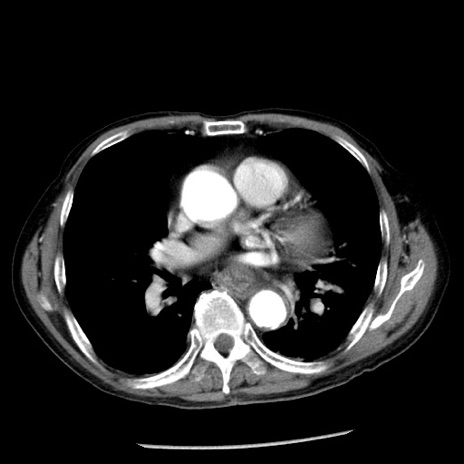

冠状断像

【症例】80歳代男性

【主訴】嘔吐

【現病歴】昨晩2回嘔吐あり、今朝になっても嘔吐あり。来院。

【既往歴】胃潰瘍

【身体所見】意識清明、BT 37.6℃、BP 166/95mmHg、HR 100bpm、SpO2 97%、腹部:平坦・軟、腸蠕動音聴取良好、圧痛なし。

【データ】WBC 21900、CRP 1.46